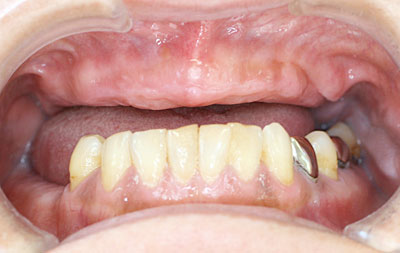

インプラント治療の進歩によって、上下顎ともインプラントを4本埋入(骨の中に植える)し、24時間以内にインプラント義歯を装着し、すぐに食べられるような治療が可能になりました。

下顎では以前から即時荷重を行って参りましたが、上顎では骨が柔らかく、さらに骨の量が足りない場合も多く、行っておりませんでした。しかし平成19年から上顎の即時荷重を開始し、平成23年3月まで50例以上行いましたが、脱落したインプラントは2本のみで、歯ぎしりをなさる患者様(1人で2本)でした。